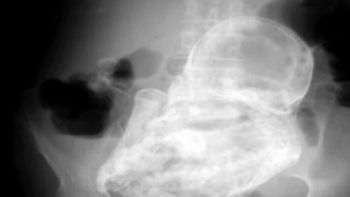

El procedimiento, en el que se unieron tendones, arterias y nervios, implicó además la reconstrucción de la estructura ósea, tanto de la mano amputada como de la muñeca. Asimismo, durante el post operatorio se realizaron todos los estudios correspondientes para evaluar la actividad fetal, con resultados normales. Romina espera una nena y ya no duda del nombre: se llamará Alma Milagros.

Los médicos le permitieron pasar Noche Buena y Navidad en su casa pero esta semana volvió a la clínica. El alta lo recibirá en unos días, después de someterse a una de las dos operaciones que le restan: la primera para restablecer la sensibilidad y lograr una fijación ósea definitiva; y la otra y última, de tipo estética, que se llevará a cabo más adelante.

Mientras tanto, está aprendiendo a utilizar la mano izquierda, porque más allá de que el reimplante haya sido exitoso, es muy difícil que recupere la motricidad fina, que permite, por ejemplo, una escritura delicada o el movimiento suave de los dedos. "Con rehabilitación logrará recobrar la fuerza para tomar objetos más grandes como un vaso o un teléfono", indicó Escudero.

Según explicó, en la próxima cirugía se volverán a suturar los nervios, y dependiendo del estado en el que se encuentren, quizás se extraigan algunos de la pierna. "Habrá que esperar entre 6 meses y un año para que la paciente recupere la sensibilidad al tacto", precisó el cirujano, quien trabaja con un equipo integrado por el traumatólogo Matías Caracciolo y los residentes de Traumatología y Plástica Reconstructiva, Martín Lovagnini y Martín Salas, respectivamente.